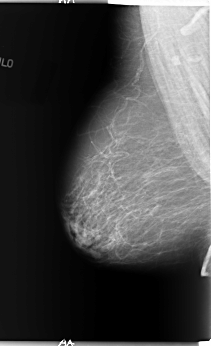

B_3089_1.RIGHT_CC

RIGHT_CC LINES 5816 PIXELS_PER_LINE 3048 BITS_PER_PIXEL 12 RESOLUTION 50 NON_OVERLAY